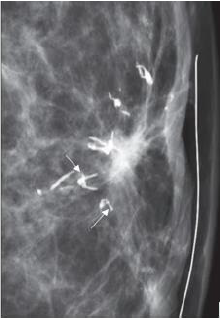

Fine pleomorphic

These are more conspicuous than the hazy amorphous calcifications and tend to have discrete shapes and measuring <0.5mm in diameter. These calcifications are irregular and vary in size and shape. They have a higher positive predictive value of 29% for malignancy and are therefore categorized as BIRADS 4b [5]; (Figure 13).

Figure 13:RMLO magnified view of a 42-yearold woman showing extensive pleomorphic microcalcifications( arrows). The diagnosis for this patient is DCIS with IDC. Image courtesy: HCG Hospitals, Bangalore.